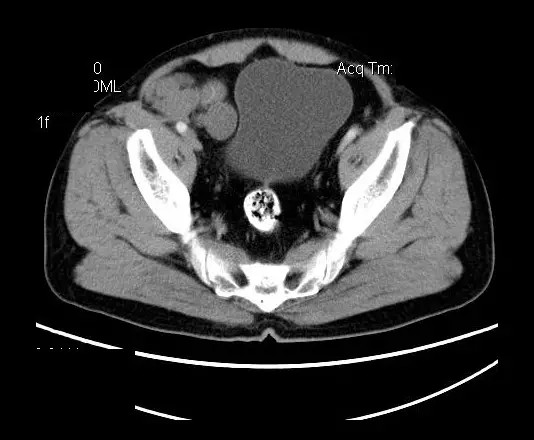

【影像表现】

盆腔右前侧及邻近腹股沟区可见多发大小不等的聚集生长的结节影,病灶呈软组织密度,边缘尚规整,分界尚清,增强扫描可见不均匀强化。膀胱局部受压,盆腔未见明显肿大淋巴结影。

平扫影像表现:Antoni A区较多病灶,在CT上呈等或略高密度影,T1WI等信号、T2WI略高信号,AntoniB区较多病灶,CT多为水样低密度、T1WI低信号、T2WI明显高信号。

增强影像表现:神经鞘膜肿瘤增强后,由于Antoni A区与B区以不同比例混合而强化不一,呈不均匀斑片状,条状强化。Antoni A 区富血供,中等或明显强化,Antoni B区乏血供,强化多不明显。